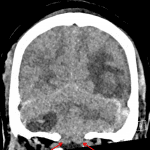

- Acute nondepressed occipital bone fracture extending into the left lambdoid suture with widening of the left occipitomastoid suture and possible extension into the mastoid temporal bone

- Acute left temporo-parieto-occipital intraparenchymal hematoma with surrounding vasogenic edema

- Small volume acute subdural hemorrhage layering over the bilateral cerebral convexities, along the interhemispheric falx, and along the bilateral cerebellar tentorial leaflets

- Mixed density right greater than left extra-axial infratentorial collections with layering low density on the right

- Cerebellar tonsillar and upward transtentorial herniation with crowding of the foramen magnum and effacement of the fourth ventricle and basal cisterns

- Trace blood products layering in the occipital horn of the right lateral ventricle

- Left frontal approach ventriculostomy catheter traverses the foramen of Monro terminating in the region of the suprasellar cistern with low density along the catheter track. Slight enlargement of the temporal horns of the lateral ventricles

- Multifocal scalp contusion with skin staples along the high posterior scalp

- Partial opacification of bilateral mastoid air cells without definite temporal bone fracture

- Multicompartmental hemorrhage with tonsillar herniation

Acute nondepressed occipital bone fracture extending into the left lambdoid suture with widening of the left occipitomastoid suture and possible extension into the mastoid temporal bone.

Acute multicompartmental intracranial hemorrhage with the following components: left temporo-parieto-occipital intraparenchymal hematoma with surrounding vasogenic edema, small volume acute subdural hemorrhage layering over the bilateral cerebral convexities (measuring x mm on the right and x mm on the left), along the interhemispheric falx, and along the bilateral cerebellar tentorial leaflets, trace blood products layering in the occipital horn of the right lateral ventricle, and right greater than left extra-axial infratentorial hematomas. Layering low density in the right posterior fossa collection is concerning for unclotted blood which may relate to hyperacute hemorrhage or coagulopathy.

Extensive posterior fossa mass effect resulting in cerebellar tonsillar and upward transtentorial herniation with crowding of the foramen magnum and effacement of the fourth ventricle and basal cisterns.

Left frontal approach ventriculostomy catheter traverses the foramen of Monro terminating in the region of the suprasellar cistern with edema/developing gliosis along the catheter track. Slight enlargement of the temporal horns of the lateral ventricles.

Partial opacification of bilateral mastoid air cells without definite temporal bone fracture.

Multifocal scalp contusion with skin staples along the high posterior scalp.